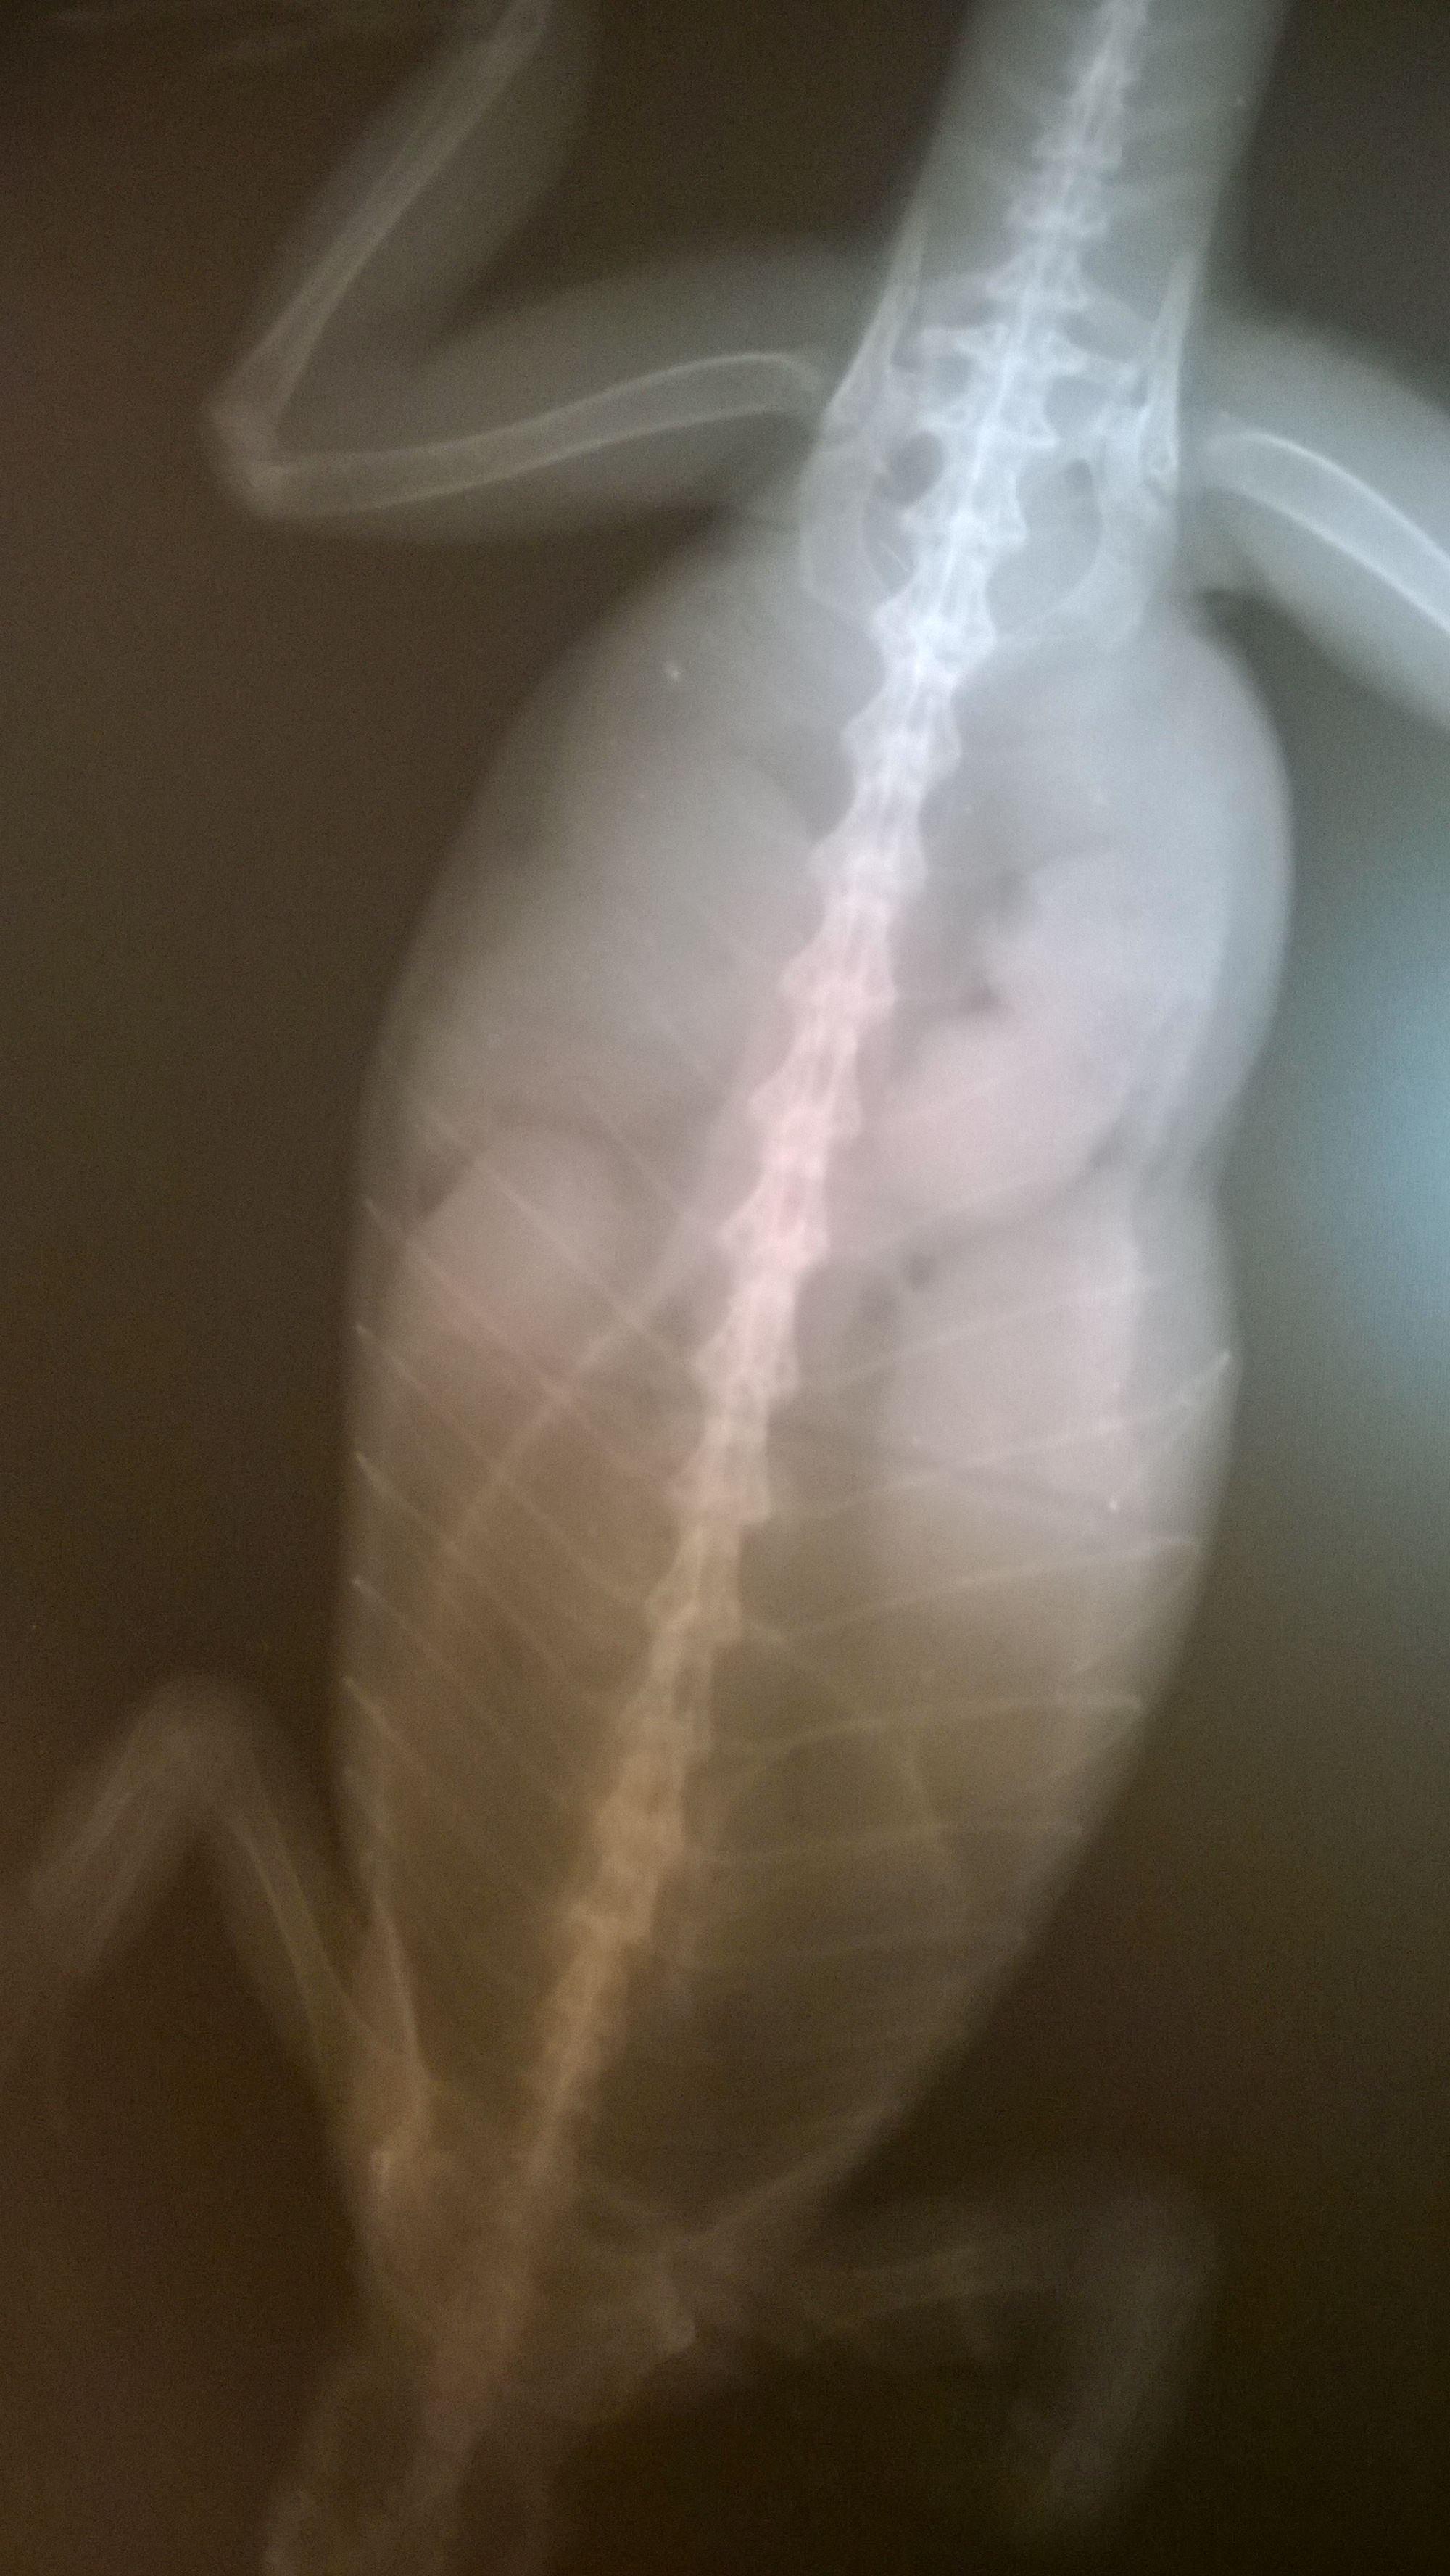

Měsíc mi nejedla samička leguána. Začalo se jí nadouvat břicho. Na snímku RTG se ukázalo že má břicho plné kuliček. Všichni jsme si mysleli, že to jsou vajíčka a druhý den měla jít na vyoperování s kastrací.

Avšak večer se zhoršil její stav, nedokázala spát v leže. Byla nahrbená a stála na natažených předních nohách. Před operací se udelal RTG snímek znovu a kuličky se změnily v jak kdyby pospojované patvary (viz snímek ve fotogalerii). Lékař pomocí endoskopie prohlédl břicho co tam tedy je. Nenašel známky po zbytcích roztrhaných vajíček, krev ani ve vejcovodech nic nebylo. Jak kdyby to vypadalo, že to jsou tukové vaky nebo je možnost prý, že může být tělo plné zánětu?? Břicho má stále velké, hrbí se a kroutí stejně jak večer. Apatická není. (dnes po uspání a endoskopii)

V Boskovicích, které na takové případy rozhodně NEDOPORUČUJI, by ji nechali s plnými vejcovody shluků snad nevyvíjejících se vajec, kdy mi při endoskopii vyvrátili plné vejcovody. Chudera, nyní je už po operaci - kastrace a vyjmutí plných vejcovodů, léčba antibiotiky.

Hmota, kterou z ní vytáhli měla 80g (její původní váha byla s tímto 380g, tak je dost znatelný úbytek). Do teď opravdu nechápu, že na původní endoskpii u jíného veterináře tohle v jejím břiše neviděl???!! Strašné.